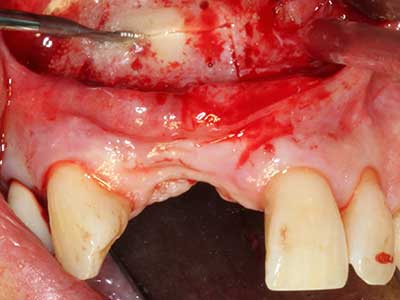

En la extracción de bloques óseos la piezocirugía también presenta ventajas adicionales: Además de la alta precisión en la osteotomía que ya se ha descrito antes, se ha comprobado que el uso de los delgados insertos de sierra resulta especialmente cuidadosas con el hueso. Frente a esto, sobre todo cuando se usan las fresas de Lindemann, cabe esperar pérdidas en la extracción significativamente más altas debido al mayor grosor de la parte frontal del cabezal (Lakshmiganthan, Gokulanathan et al. 2012). La separación basal que se necesita en particular en los injertos de bloque extraídos de forma retromolar se ve facilitada mediante sierras perpendiculares especialmente previstas a tal fin, lo que permite considerar que la cirugía piezoeléctrica es un procedimiento preciso y seguro para la obtención de bloques de hueso en el área retromolar (Happe 2007) (fig. 1-12).

Aplicación: Partición ósea / Cortical Split

El tejido óseo no solo tiene un contenido puramente mineral, sino que también presenta una importante proporción de fibras de colágeno. Esto no solo garantiza una buena resistencia a la presión, sino también una cierta flexibilidad, que puede aprovecharse para la realización de aumentos. En la plastia de expansión clásica a efectos de una partición ósea, la cresta maxilar atrofiada se divide en su eje longitudinal y, tras alcanzar una profundidad de osteotomía suficiente, se extiende con cuidado (fig. 13-16), en un caso ideal sin desperiostizar de forma visible el maxilar (Brugnami, Caiazzo et al. 2014, Stricker, Fleiner et al. 2014). Los sistemas de tornillos y placas con distancia de expansión creciente han demostrado su eficacia para distanciar entre sí las dos tablas óseas por debajo del umbral de rotura. Por regla general, se requieren anchuras de hueso residual de al menos 3 a 4 mm (Chiapasco, Zaniboni et al. 2006) para garantizar una flexibilidad y una cobertura ósea suficientes de los implantes que van a incorporarse. En caso necesario, una osteotomía de descarga vertical unilateral o bilateral puede mejorar la flexibilidad. Como alternativa a la técnica clásica se ha descrito una combinación con otras técnicas de aumento, sobre todo en la parte bucal.

Con el uso de sierras piezoeléctricas la división se efectúa de forma especialmente cuidadosa y sin pérdidas importantes de las dimensiones, por lo que no se han encontrado diferencias significativas entre los implantes realizados en el maxilar dividido y en la cresta alveolar no deficitaria (Chiapasco, Zaniboni et al. 2006, Danza, Guidi et al. 2009). No obstante, precisamente en la partición profunda y limitada de forma local, es preciso asegurarse de que exista una adecuada irrigación por agua para evitar que se produzcan sobrecargas térmicas en las áreas de osteotomía apical.